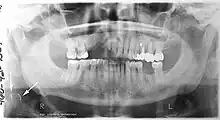

A basic panoramic radiograph

Minimally-displaced fracture in right mandibular. Arrow marks fracture, root canal on central incisor, teeth to the left of fracture do not touch